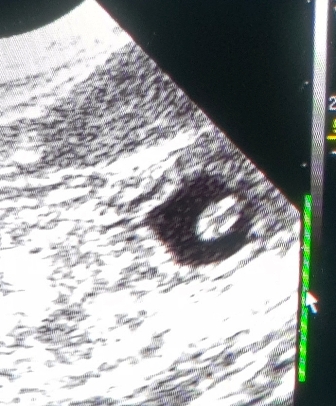

Denn auf dem Ultraschall sind selten alle zu sehen.

Welche Freude beim Ultraschall im Wohnzimmer (meist schauen viele mit zu..;)

wenn die schwarzen Fruchthüllen mit den kleinen "Gummibärchen" drin zu sehen sind!!!!

Meine Kinder haben mir vor Jahren ein kleines Ultraschallgerät geschenkt,

welches für diesen Zweck hervorragend geeignet ist!

Jedesmal ist es für mich eine riesige Freude :)